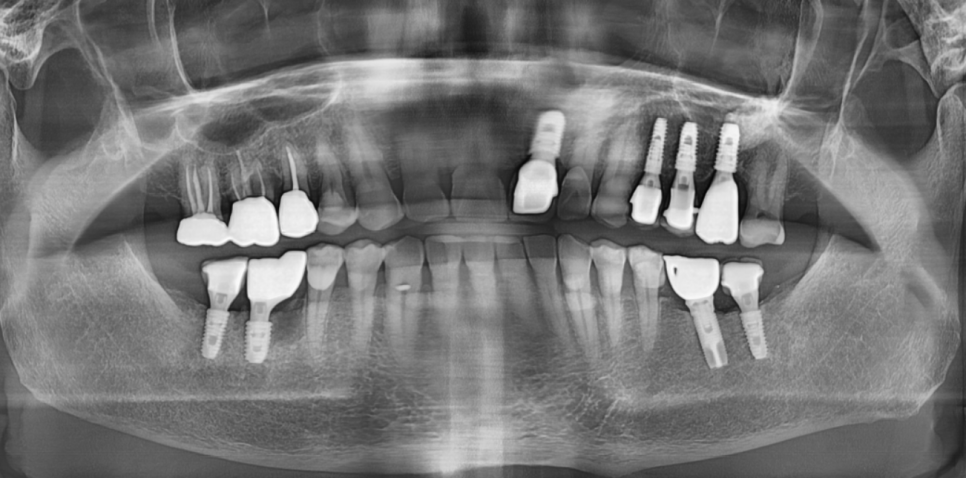

첫번째 주의사항으로 임플란트 구멍 살피기

추후 임플란트 수리에 필요한 구멍으로

레진이라는 재료를 사용하여 메꿔드리는데요.

이 표면이 닳거나 탈락하여

음식물이 낄 수 있습니다.

때문에 재료가 탈락하면 명일동 치과를 방문해주셔야해요.

(음식물이 끼거나 임플란트 주변으로 냄새가 나면 오세요~)